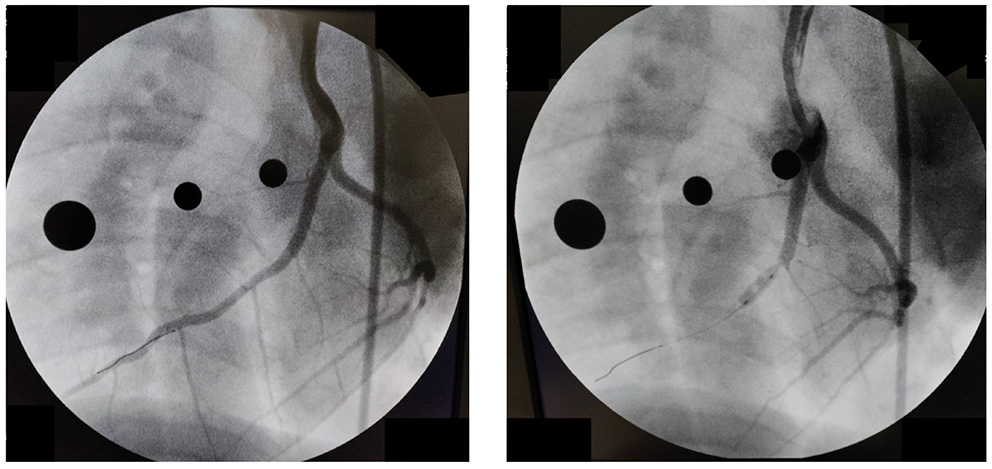

Data acquisition was accomplished in an acute experimental setting of mycardial infarction (MI) pre- and immediately post-ischemia (during reperfusion) in one Yorkshire swine (intact female, 30 kg, approximately 3 months old) in Dr. Emter's lab. The MI was created using an established ischemia-reperfusion protocol with modifications (46). The animal was sedated with 7.0 mg/kg Telazol intramuscular (IM) followed by 0.03 mg/kg buprenorphine IM for pain control. Anesthesia was induced with 2.0 mg/kg propofol intravenous (IV) and maintained by constant rate infusion (CRI) of 4–20 mg/kg. The animal was mechanically ventilated with 100% oxygen at a rate of 8–12 breaths per minute with tidal volume 10–20 mL/kg and 20–25 cm H20 pressure. The left anterior descending (LAD) coronary artery was completely occluded just distal to the 1st diagonal (D1) for 90 min using a balloon angioplasty catheter (3.5 mm x 8 mm, Abbott Trek) followed by reperfusion. Placement of the balloon was accomplished using a 6F guide catheter (Boston Scientific) introduced into the LAD coronary artery under fluoroscopic guidance (see Figure 3). During the ischemia-reperfusion procedure, ECG and vital signs were continuously monitored and the animal was cardioverted to prevent fatal arrhythmia using a standard 200 Joule biphasic defibrillator. Transthoracic M-mode echocardiography was performed pre- and post-MI in the supine/right lateral position as previously described (44, 45, 47–50). Short-axis two-dimensional M-mode images were recorded at the mid-papillary level using a GE Vivid I Ultrasound system with a 2.5-MHz transducer and all analyses were performed offline using GE EchoPac Software. Left ventricular fractional shortening % was calculated from M-mode recordings.

Figure 3

Angiography pre-(Left) and post-(Right) occlusion of the Left Anterior Descending Coronary artery.